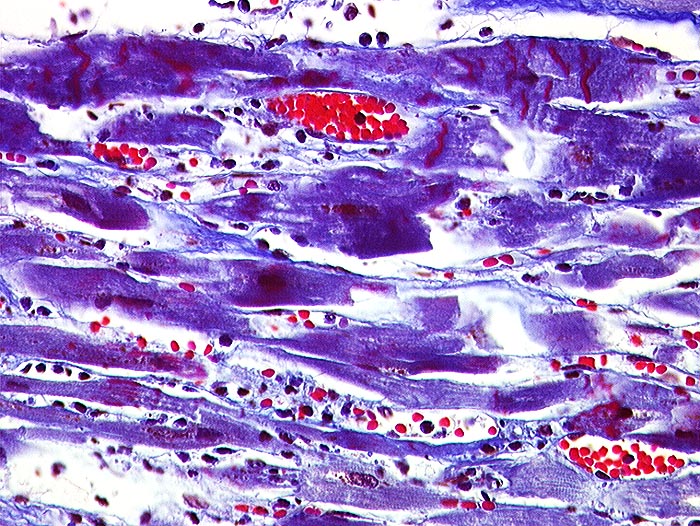

Akuter Myokardinfarkt: Kontraktionsbänder

Quer zu den Myozyten verlaufende rot gefärbte Kontraktionsbänder. Granulozytäres Infiltrat rechts im Bild.

Paninfarkt bei schwer stenosierender Koronarsklerose mit Abgangstenose beider Hauptäste. Alter Verschluss der Arteria coronaria dextra.

Kontraktionsbänder sind nach 30 Minuten, zelluläre Infiltrate nach minimal 3 Stunden sichtbar. Kontraktionsbänder entstehen, wenn das hypoxisch geschädigte Myokard sich noch kontrahiert, aber nicht mehr relaxieren kann.